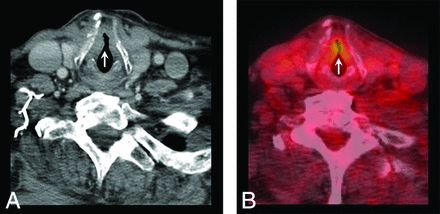

NI-RADS primary site category 2a: superficial mucosal abnormality. Primary T2 larynx squamous cell carcinoma status post chemoradiotherapy. A, CECT showed subtle irregularity of the anterior commissure and anterior true vocal cords bilaterally (arrow). B, Corresponding fused PET image shows focal mucosal uptake (arrow). After direct visualization revealed suspicious mucosal findings, the biopsy showed persistent disease. Although this lesion does demonstrate focal avid FDG uptake, it is in a special category of mucosal abnormality. In the published NI-RADS 1.0 by Aiken et al,5 these are scored as 2a because the linked management recommendation is direct visualization.

Finally, NI-RADS 3 is reserved for a discrete, nodular, robustly enhancing lesion (Fig 7A) with marked FDG uptake if PET was also performed (Fig 7B), and the recommendation is for biopsy. In the neck, NI-RADS 3 is a new or enlarging lymph node (Fig 8A) with marked FDG uptake if PET is combined (Fig 8B). The positive predictive value for NI-RADS 3 primary site lesions was lower (54.6%) than for the neck (70%); this finding likely reflects the more complex posttreatment imaging appearance at the primary site. Overall, we believe that the NI-RADS template yielded a reasonable rate of recommending biopsy. Only 32 of 618 possible targets (5.2%) were scored category 3 with biopsy recommendation, balanced against a relatively high positive predictive value (54.6% for the primary site, 70% for the neck).

NI-RADS primary site category 3: discrete enhancing lesion. T4a larynx squamous cell carcinoma, status post total laryngectomy, bilateral neck dissection, and chemoradiotherapy. A, CECT shows a 1-cm discrete rounded hyperenhancing nodule along the lateral border of neopharynx, deep to the flap (arrow). B, Fused PET images show focal high FDG uptake (arrow). This was given a category 3 score, and endoscopic biopsy demonstrated recurrence.